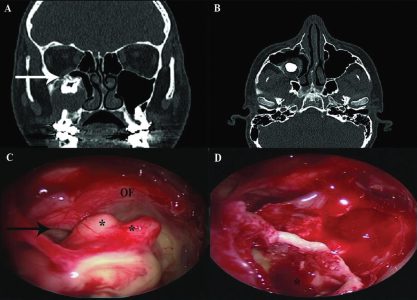

לאחר מספר בדיקות שעבר במקום, התגלתה הסיבה המפתיעה שגרמה לבעיה: שן שצמחה בחלל הסינוס המקסילרי מצדו השמאלי של האף שיצרה ציסטה דנטלית גדולה מאוד. בניתוח אנדוסקופי זעיר פולשני שבוצע ללא חתך חיצוני, אלא דרך הנחיריים, ד"ר מוחמד מסאלחה, מומחה לניתוחים אנדוסקופיים של האף, סינוסים ובסיס הגולגולת, ביצע פתיחה של מערת הלסת משמאל לחלל הסינוס המקסילרי – וכך נעקרה השן. הד"ר מסביר כי השן הוצאה בשלמותה דרך האף, הציסטה רוקנה מהדלקת והאזור נוקה וטופל. למחרת, שוחרר יוני לביתו ותוך שבוע, חלפו הכאבים.

"לאבחנת המחלה דרושות בדיקות דימות. צילום רנטגן פשוט המכוון לסינוסים, יכול לאבחן את נוכחות השן בחלל הסינוס. אולם, על מנת לקבל אבחנה ודאית הכוללת מיקום מדויק של השן, גבולותיה, גבולות מערת הלסת והיקף התהליך הדלקתי, דרושה בדיקת CT לסינוסים ולסת עליונה, הנחשבת לבדיקה העדיפה לצורך אבחון שיניים אקטופיות בסינוס המקסילרי ובאבחנת סינוסיטיס. בדיקה כזו, ניתן לבצע באמצעות מכשיר CBCT, מכשיר CT בעל קרינה מינימאלית, הייעודי למצבים בריאותיים אלה, הנמצא במרכז הרפואי א.ר.ם. לאחר האבחנה, הטיפול כירורגי.

ד"ר מסאלחה מציין כי בעבר טופלו מקרים מסוג זה על ידי רופאי שיניים או מנתחי פה ולסת, לרוב היה מדובר במטופלים שאובחנו במקרה, במהלך בירור דנטלי. הטיפול כלל גישה כירורגית דרך חלל הפה, על ידי חתך כירורגי מעל רכס השיניים בצד המעורב, חדירה למערת הלסת, עקירת השן וניקוי הסינוס. אולם, עם התפתחות הגישה האנדוסקופית, בשני העשורים האחרונים, יותר ויותר מקרים של שיניים אקטופיות טופלו בגישה זו, דרך חלל האף. במהלך השיטה, רופא אא"ג המומחה למחלות האף והסינוסים (רינולוג) משתמש בסיבים האנדוסקופים יחד עם ציוד כירורגי דק ומיוחד, כדי לפתוח את הסינוס החולה, לעקור את השן האקטופית ולנקות את הסינוס לחלוטין. "מדובר בשיטה זעיר פולשנית ללא חתכים חיצוניים, הכרוכה בכאבים קלים בלבד המשפרת את הסיכוי לריפוי הסינוס באופן פיזיולוגי טוב וללא סיבוכים. בנוסף, הגישה האנדוסקופית משמרת את ריריות הפה ואת האנטומיה הדנטלית כפי שהן, מה שמקל על כל תהליך טיפולי או שיקומי דנטלי בעתיד", מציין הד"ר.